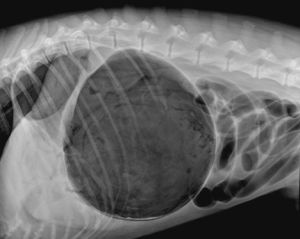

擴張是由於胃內液體,食物或氣體聚積,使胃發生過度擴張所引起的一種疾病。品種較大的犬多見。

病犬表現腹痛嚎叫、不安,可見有噯氣、流涎和嘔吐、呼吸淺快、心動過速、結膜紺紅、腹圍增大,觸診腹部動物表現疼痛感。嚴重病例可因脫水、酸中毒、胃破裂及心力衰竭死亡。